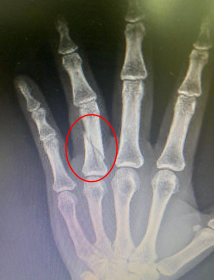

魏女士从亲朋好友处得知betway在线登陆的手外科技术非常好,于是前来我院就诊。手外二病区的熊祖国医生接诊,摄片显示:左环指近节斜行骨折,并有一定程度的移位。熊医生告知患者,此类斜行骨折属于不稳定性骨折,需要内固定手术治疗,内固定又分为克氏针内固定、钢板内固定等不同的方法,各有优缺点。克氏针内固定可以微创,但是牢固性较差,术后常需要石膏托辅助固定,不能早期康复锻炼,不利于功能锻炼恢复。而钢板内固定骨折固定坚强牢固,术后不需石膏托辅助外固定,可早期康复锻炼,利于手部功能恢复,但是通常存在手术瘢痕。

术前